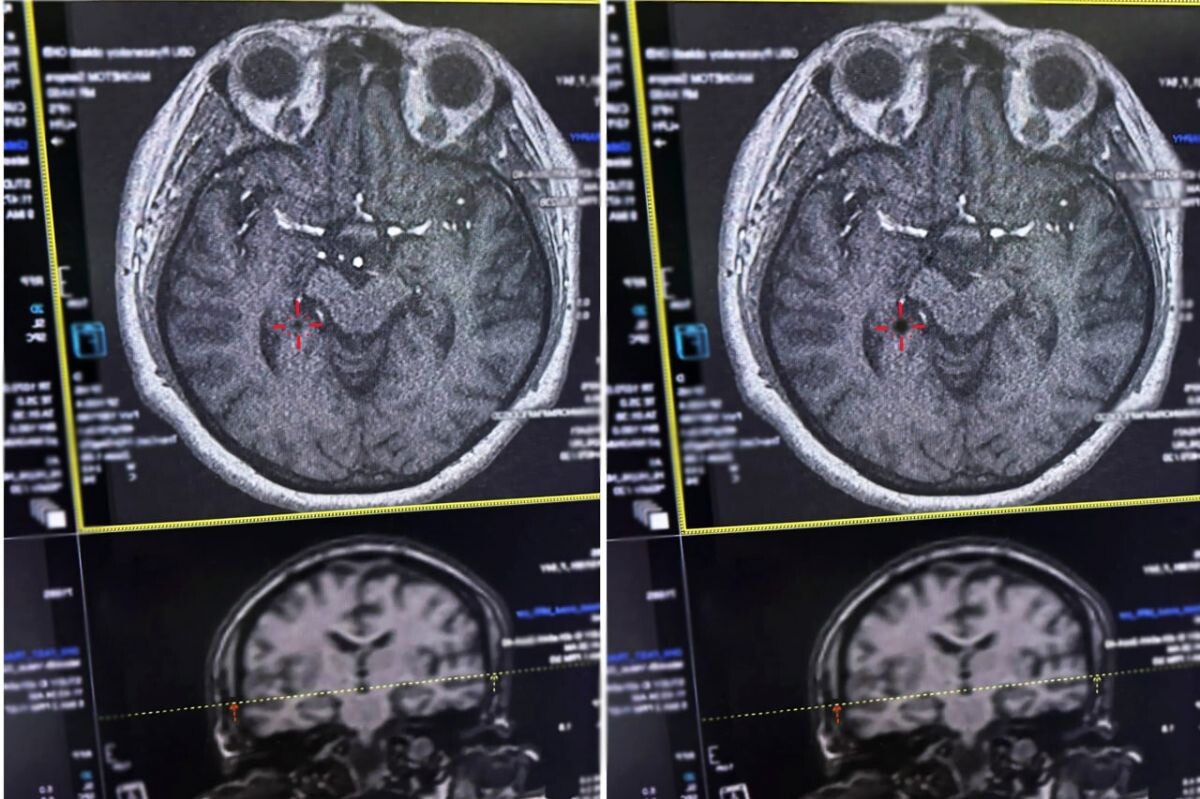

В Рязани врачи Областной клинической больницы спасли женщину, которую в магазине ударил инсульт. Об этом сообщает пресс-служба больницы. Женщина ходила за покупками с дочкой. По словам пациентки, она почти не ощутила дискомфорта — у неё просто закружилась голова, и она потеряла сознание. Тревогу забила находившаяся рядом дочь. «Она придерживала мне голову и звала на помощь, просила вызвать «скорую», - вспоминает женщина. Во время транспортировки в больницу у женщины была обездвижена правая сторона тела и наблюдалась сильнейшая головная боль. Медикам удалось помочь пациентке в течение критически важных 4,5 часа после начала инсульта. По информации врачей, при ишемическом инсульте кровоток по сосуду, питающему мозг, прекращается. Лишённый кислорода участок нервной ткани начинает быстро погибать. В этот момент крайне важно успеть восстановить кровоснабжение, растворив тромб специальными препаратами, и сделать это можно только в первые часы. Рязанцам напомнили, ключевые признаки инсульта.

По информации врачей, при ишемическом инсульте кровоток по сосуду, питающему мозг, прекращается. Лишённый кислорода участок нервной ткани начинает быстро погибать. В этот момент крайне важно успеть восстановить кровоснабжение, растворив тромб специальными препаратами, и сделать это можно только в первые часы.